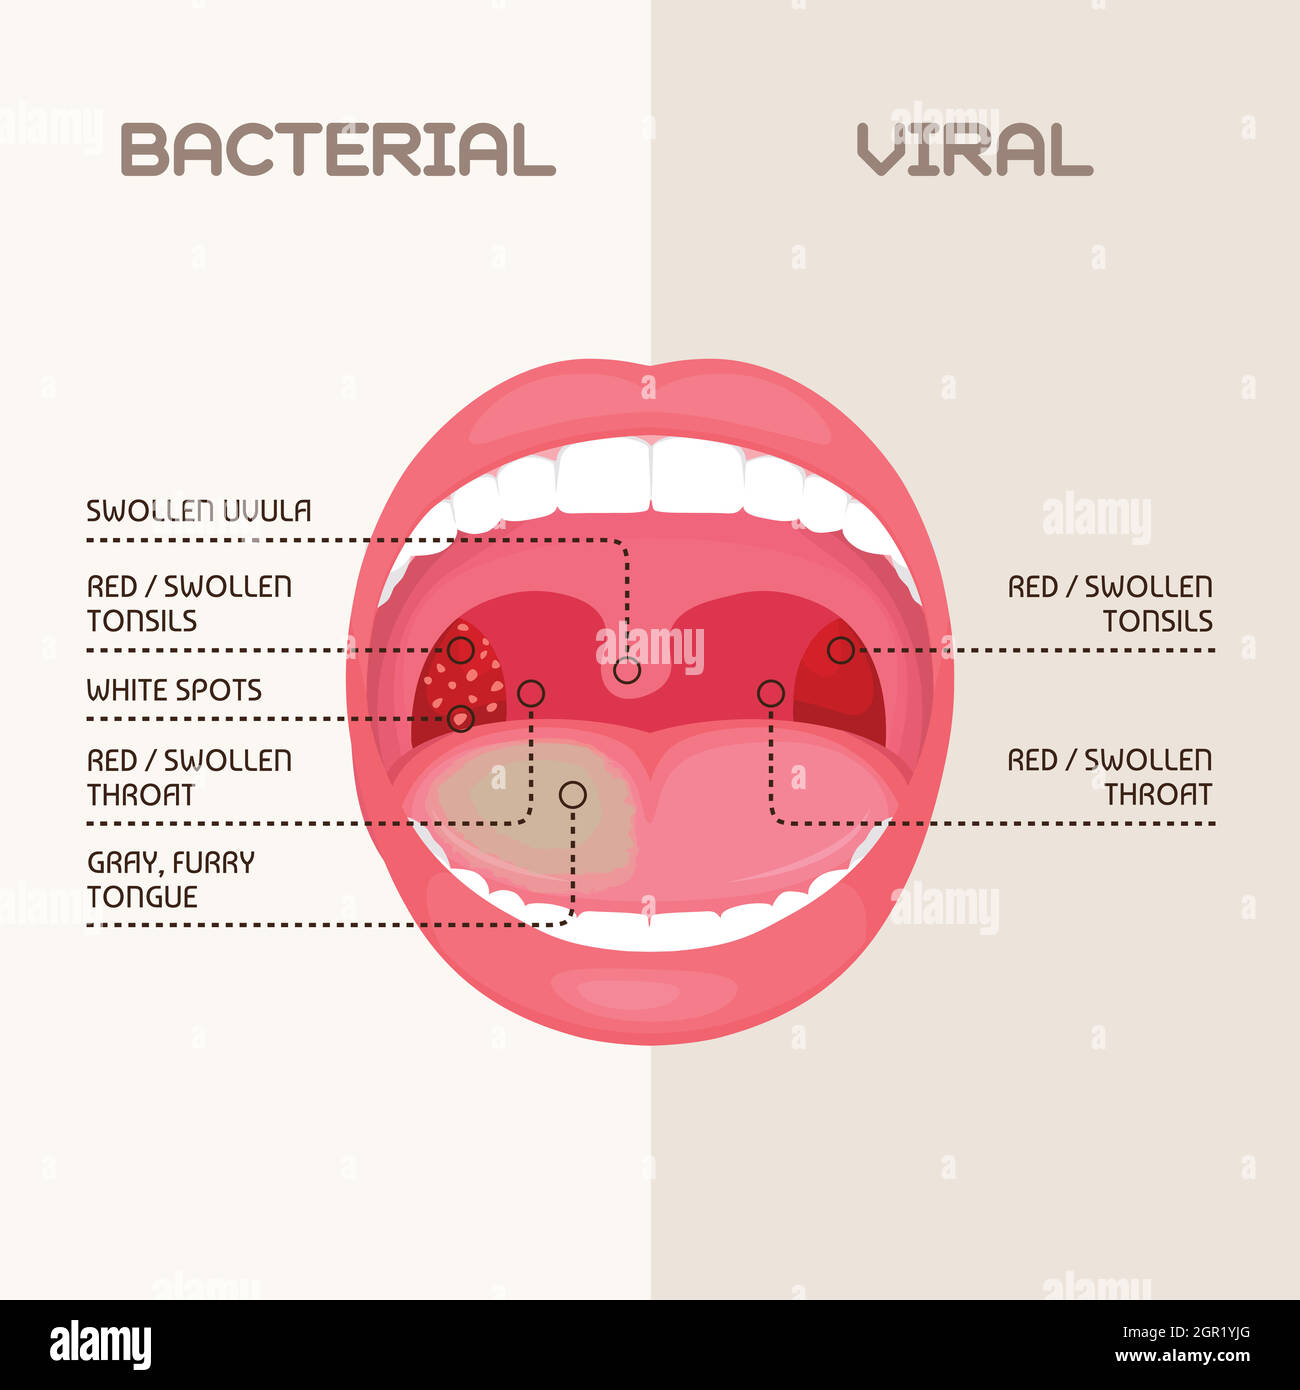

Medizinische Darstellung der Symptome einer viralen und bakteriellen Tonsillitis, auch virale Amygdalitis und bakterielle Amygdalitis genannt, mit den Erregern t Stock Vektorhttps://www.alamy.de/image-license-details/?v=1https://www.alamy.de/medizinische-darstellung-der-symptome-einer-viralen-und-bakteriellen-tonsillitis-auch-virale-amygdalitis-und-bakterielle-amygdalitis-genannt-mit-den-erregern-t-image352264760.html

Medizinische Darstellung der Symptome einer viralen und bakteriellen Tonsillitis, auch virale Amygdalitis und bakterielle Amygdalitis genannt, mit den Erregern t Stock Vektorhttps://www.alamy.de/image-license-details/?v=1https://www.alamy.de/medizinische-darstellung-der-symptome-einer-viralen-und-bakteriellen-tonsillitis-auch-virale-amygdalitis-und-bakterielle-amygdalitis-genannt-mit-den-erregern-t-image352264760.htmlRF2BD3188–Medizinische Darstellung der Symptome einer viralen und bakteriellen Tonsillitis, auch virale Amygdalitis und bakterielle Amygdalitis genannt, mit den Erregern t

Kehle bakterielle und virale Infektion, Mandeln Entzündung. Stock Vektorhttps://www.alamy.de/image-license-details/?v=1https://www.alamy.de/kehle-bakterielle-und-virale-infektion-mandeln-entzundung-image444439928.html

Kehle bakterielle und virale Infektion, Mandeln Entzündung. Stock Vektorhttps://www.alamy.de/image-license-details/?v=1https://www.alamy.de/kehle-bakterielle-und-virale-infektion-mandeln-entzundung-image444439928.htmlRF2GR1YJG–Kehle bakterielle und virale Infektion, Mandeln Entzündung.